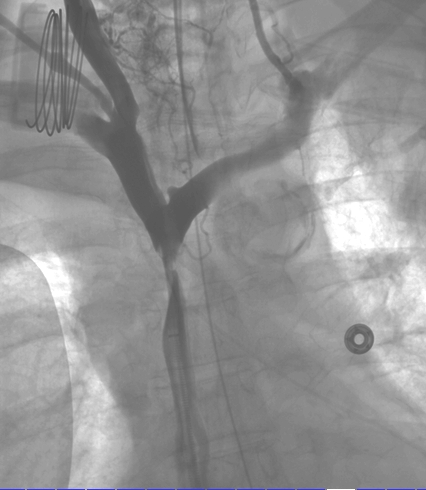

The diagnosis is usually clinical. Once clinical suspicion arises, imaging needs to be utilized. Sometimes we begin to suspect this diagnosis because of a combination of typical clinical signs and symptoms and a widened mediastinum on plain chest radiograph. However, the best imaging study for diagnosing an obstruction in the superior vena cava or compressing mass is CT with intravenous contrast. MR and PET-CT may have their value in specific cases, though. Other than the diagnosis of superior vena cava compression or thrombosis, the cause needs to be identified fully. Therefore, many times biopsy and pathological tests are needed to compliment imaging. Tissue may be obtained in various methods including from sputum, pleural fluid, mediastinoscopy or open surgical biopsy. Before intervention (see ‘treatment of superior vena cava syndrome’), venography may be needed, although it is sometimes a combined diagnostic and therapeutic intervention.

We use superior vena cava stenting in patients with SVCS secondary to malignancy as a rescue procedure in patients with severe swelling or shortness of breath. Stents may be used either as secondary, rescue, treatment when chemotherapy and or radiation have failed or as first line treatment. After successful stenting, symptoms are expected to resolve within 24-48 hours.

The durability of palliative superior vena cava stenting procedures is rather good considering the usual patient overall condition. Therefore, the superior vena cava syndrome does not usually return to bother the patient and proper treatment endeavors can be sought. However, recurrence happens in in 10-20% of patients, and then re-treatment is needed in a similar manner to the first one. Superior vena cava stents may be self-expanding or balloon expandable. There are several types of stents that are in use for treatment of superior vena cava syndrome. These include self-expanding stents and balloon-expandable stents. Choice of the proper stent depends on how tight the superior vena cava stenosis is, the length of the lesion and on vessel curvature.

Examples of stents that are being used for treatment of superior vena cava syndrome include the Palmaz balloon-expandable stent and the self-expanding Wallstent and memotherm stents. Despite relative ease of stent implantation and expected high frequency of relief of symptoms, it is important to remember that superior vena cava stenting does have (rare) complications. Stent occlusion is the most common complication of superior vena cava stenting (occurring in up to 33% of cases). This is secondary to thrombosis or tumor invasion. However, as stated before stent re-stenosis can be treated with options such as thrombolysis, thromboaspiration or re-stenting. There are other, rarer complications, such as stent misplacement, stent migration and rupture of the vena cava during insertion.